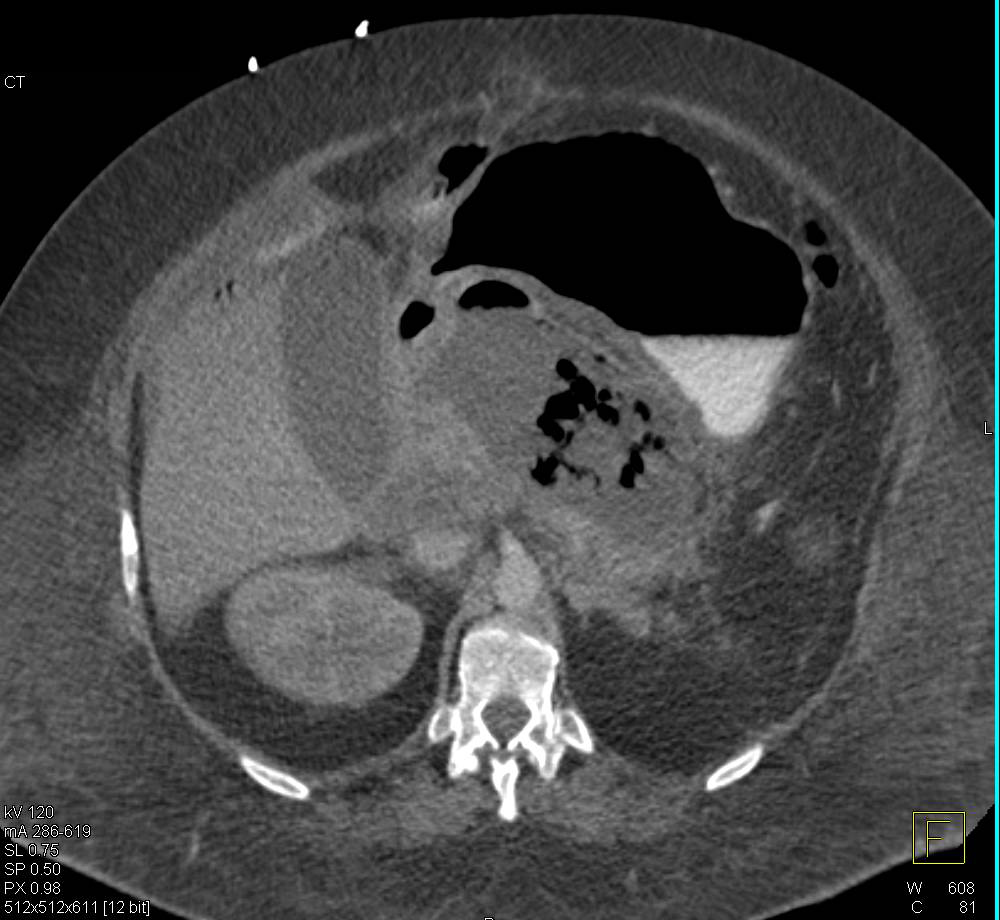

Carcinoid Tumor Near Uncinate Process Simulates a Pancreatic Mass